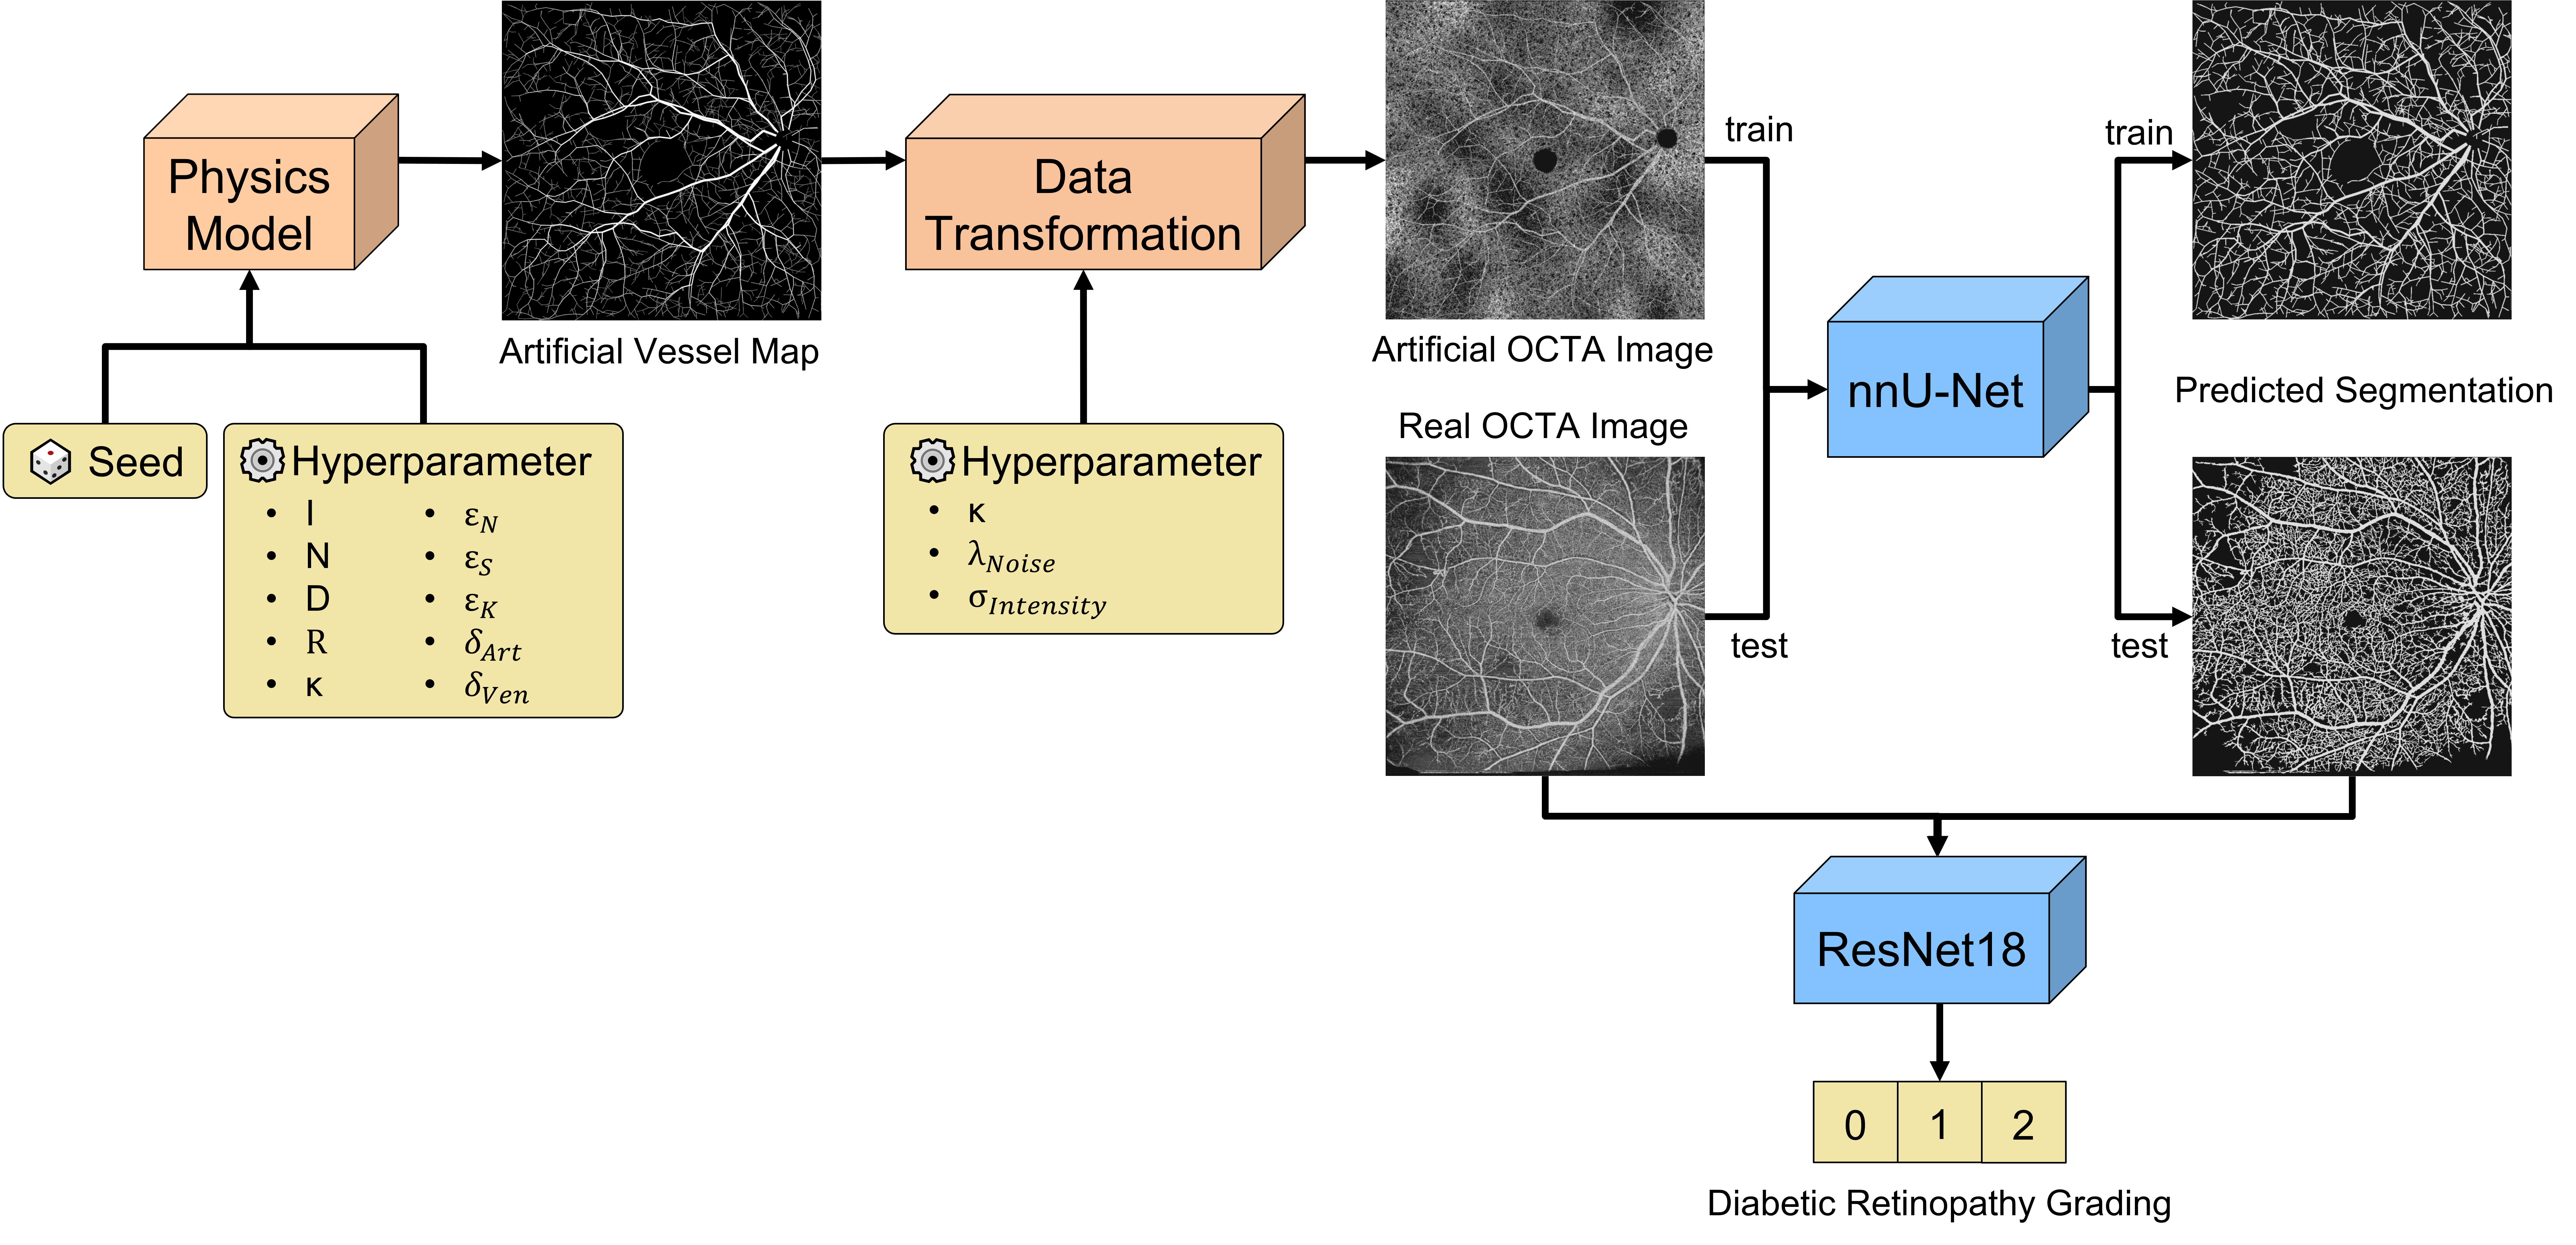

Recent studies suggest that early stages of diabetic retinopathy (DR) can be diagnosed by monitoring vascular changes in the deep vascular complex. In this work, we investigate a novel method for automated DR grading based on ultra-wide optical coherence tomography angiography (UW-OCTA) images. Our work combines OCTA scans with their vessel segmentations, which then serve as inputs to task specific networks for lesion segmentation, image quality assessment and DR grading. For this, we generate synthetic OCTA images to train a segmentation network that can be directly applied on real OCTA data. We test our approach on MICCAI 2022’s DR analysis challenge (DRAC). In our experiments, the proposed method performs equally well as the baseline model.

Diabetic retinopathy causes retinal vascular changes, and while being subtle at first, it eventually leads to dangerous vascular abnormalities and neovascularization. We hypothesize that by explicitly feeding the segmentation map of the vasculature to a deep neural network, we can provide a strong inductive bias for the network to predict the severity of DR. Recent studies suggest that early DR progression is mainly correlated with biomarkers found in the deep vascular complex (DVC), while the superficial vascular complex (SVC) is generally only affected in severe cases [1, 6]. The authors hypothesize that the DVC might be more susceptible to ischemic damage because of its anatomical proximity to the outer plexiform layer, which has a high oxygen consumption. Therefore, it becomes clear that including small capillaries in the segmentation map is vital. However, to our knowledge, there is no publicly available dataset of OCTA images with corresponding vessel segmentation that includes small capillary vessels. Merely two public datasets, namely OCTA-500 and ROSE, have been released with segmentation labels for vessels and the foveal avascular zone (FAZ), both of which unfortunately only segment the largest vessels of the SVC [7, 8]. To circumvent the problem of missing labeled data, we generate an artificial dataset ourselves. Figure 1 shows our proposed pipeline.

In our work, we investigate whether an additional input channel to our network can boost the performance of a neural network. Our proposed additional input is a segmentation map of the vasculature, including small capillaries in the retina. To extract a faithful segmentation, we use synthetic OCTA images to train a segmentation network, which can then be used to generate the additional input channel on the fly.

2.1 Synthetic Data Generation

Synthetic data generation to train segmentation networks is a vastly accepted technique to mitigate data sparsity through transfer learning in medical imaging [9, 10, 11]. Schneider et al. propose a configurable physics model to simulate the growth of vascular trees based on physical principles [12]. The blood vessel network is represented as a forest of rooted binary tree graphs that are iteratively updated based on the simulated oxygen concentration and the vascular endothelial growth factor (VEGF). Bifurcations and growth direction follow the physical laws of fluid dynamics to ensure realistic branching. From the resulting 3D graph network, it is then possible to retrieve 2D images and their ground truth segmentation maps by voxelizing the edges. This approach has proven efficient across multiple vessel segmentation tasks [13, 14, 15, 16]. Menten et al. later adapted this approach to simulate the retinal vasculature [17]. They heuristically tune the simulator’s hyperparameters to mimic the structure of the SVC and the DVC. Binary masks are used to decrease the VEGF within the FAZ, as well as the perimeter of the FOV. Using different seeds, it is possible to generate an unlimited amount of diverse vessel maps.

To bridge the domain shift from synthetic to real OCTA images, Menten et al. employ a variety of data augmentations, such as eye motion artifacts, flow projection artifacts, and changes in brightness. The background signal caused by small capillary vessels is simulated by binomial noise and convoluted by a Gaussian filter since it is computationally intractable to simulate them. After training a U-Net on a synthetic dataset, the network can extract detailed segmentation maps on real data.

We adopt a modified algorithm version and tune it to realistically represent ultra-wide OCTA images. Instead of setting the roots of the trees on the image’s border, we simulate the optical nerve, letting all vessel trees originate from there.

Instead of limiting bias fields to the outer rings of the FOV, we randomly apply them at every possible position as part of data augmentation. Furthermore, we employ random rotation, flipping, elastic transformation, scaling, and motion artifacts during the training of the segmentation network. We use a variation of the very successful U-Net architecture [18] and follow the guidelines of nnU-Net to configure our network optimally for the given task [19].